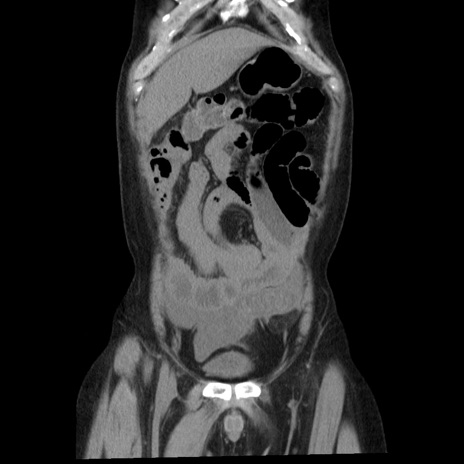

横断像